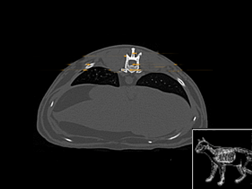

Atlas thorax du chien SCTO

Scanner tissus osseux

>> 23 coupes

Atlas thorax du chien SCTM

Scanner tissu mou

>> 22 coupes

Atlas thorax du chat SCTO

Scanner tissu osseux

>> 30 coupes

Atlas thorax du chat SCTM

Scanner tissu mou

>> 30 coupes